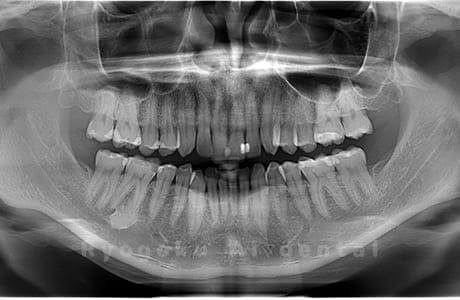

Case04

- 原因

- 上顎の親知らず、下顎の水平埋伏の親知らず

- 治療内容

- 上顎の親知らず、下顎の水平埋伏の親知らずを抜歯したケースです。

<リスク・副作用>

手術後は痛み、腫れ、痺れなどの副作用が生じる場合があります。